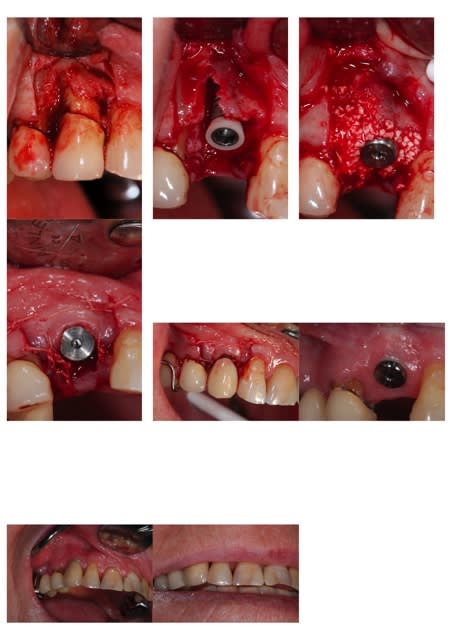

je te propose ce cas que j'ai achevé il y a 2 mois; tu verras que la notion de limite est variable, sauf celle du blocage primaire, d'où cette proposition de mise en esthétique uniquement avec un bon blocage primaire;

dans le cas présenté, je n'ai bien évidemment pas fait de mise en esthétique, j'ai simplement mis une PAP d'une dent, puisque la 14 est une CCM où je ne pouvais pas faire de collage

j'ai mis du ß TCP sans membrane, j'ai eu une très légère récession gingivale que l'utilisation des TBR Zircone autorise sans soucis avec un sourire non gingival

la pose a été faite 6 mois plus tard

Eii le tal - Eugenol

Pr  op suloxf - Eugenol

Pose cl1jmq - Eugenol

Comblement ueqajm - Eugenol

Sutures bdm18l - Eugenol

Pap feptx8 - Eugenol

6 mois kx5itc - Eugenol

Pose qmceht - Eugenol

Sourire dqz88s - Eugenol